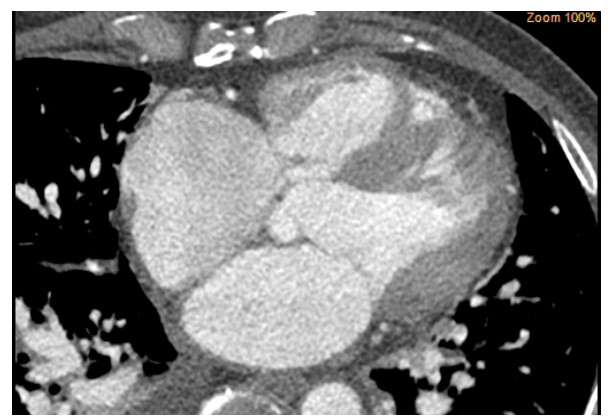

术前心脏计算机断层扫描血管造影(computed tomographyangiography, CTA)检查未能明确诊断右乏氏窦瘤破裂(图 4),这给临床医生带来一定困惑。经急诊超声心动图检查及临床医生全面评估后行右乏氏窦瘤破裂修复术和主动脉瓣成形术。取适当大小的牛心包补片,间断褥式缝合修补破口及室间隔夹层,并行主动脉瓣成形术。术中经食道超声心动图显示窦瘤破裂修补完好,分流消失,主动脉瓣瓣叶开闭良好,反流消失。术后1个月复查,二维超声心动图显示主动脉短轴切面:右乏氏窦瘤破裂修补处回声增强,连续性好;CDFI:该处分流消失。主动脉瓣瓣叶开闭正常。胸骨旁四腔心切面显示如上(图 5),室间隔回声稍不均质,室间隔夹层动脉瘤完全塌陷,未见夹层动脉瘤显示。

| 图 4 CTA未能明确诊断右乏氏窦瘤破裂 |

本例心脏CTA漏诊,分析原因包括:一是受心脏搏动、呼吸运动伪影干扰;二是检查时可能处于分流量少的心动周期实相。此外CTA存在电离辐射与过敏风险,在基层医院并非首选,临床诊断时需结合患者情况与检查优势综合选择,避免因单一检查手段导致漏诊或误诊。